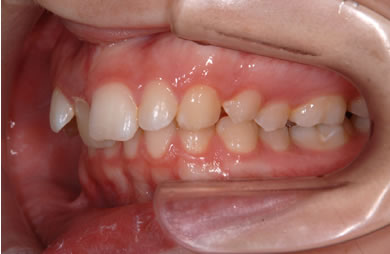

| 性別/年齢 | 女性 / 19歳 | ||||||||||||||||||||||||||||||||

| 主訴 | 上のデコボコの歯を綺麗にしたい。 | ||||||||||||||||||||||||||||||||

| 治療方針 | 上顎の歯の傾斜を正常に治す事で下顎を正常な位置に推進させ、非抜歯にて治療を行う。また、上下の顎のずれの治療のため、装置にゴムを使用し審美的・機能的に良い咬合を獲得させる。 | ||||||||||||||||||||||||||||||||

| 治療内容 | 唇側矯正(シルバー) | ||||||||||||||||||||||||||||||||

| 治療期間 | 1年9ヶ月 |